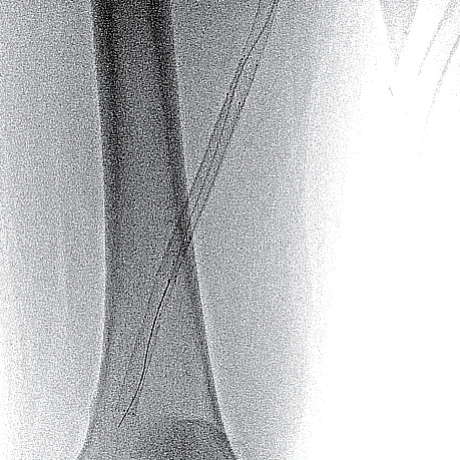

- 4 Fr IMA(内胸動脈用)造影カテーテル併用し0.014 inch wireを閉塞内へ進入し、ステント近位まで比較的容易にワイヤリングすることに成功(血管内超音波(IVUS)にてintra-plaqueであることを確認)

- ステント近位端は非常に硬化しており、0.014 inch wireでのknuckle wiringおよび0.035 inch wire のtail 側でもステント内へ進入できず

- 4 Fr IMA造影カテーテルにマイクロカテーテル併用下でtapered coil typeの0.018 inch wireにてなんとかステント近位端を通過(図2)